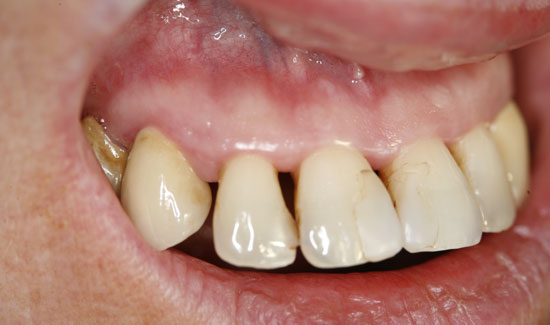

Abb. 2: Klinischer Aspekt der Regio 12, Entstehung von Gasblasen am entzündeten Gewebe. Fortlaufende Absaugung in der Nähe des Einsatzgebietes